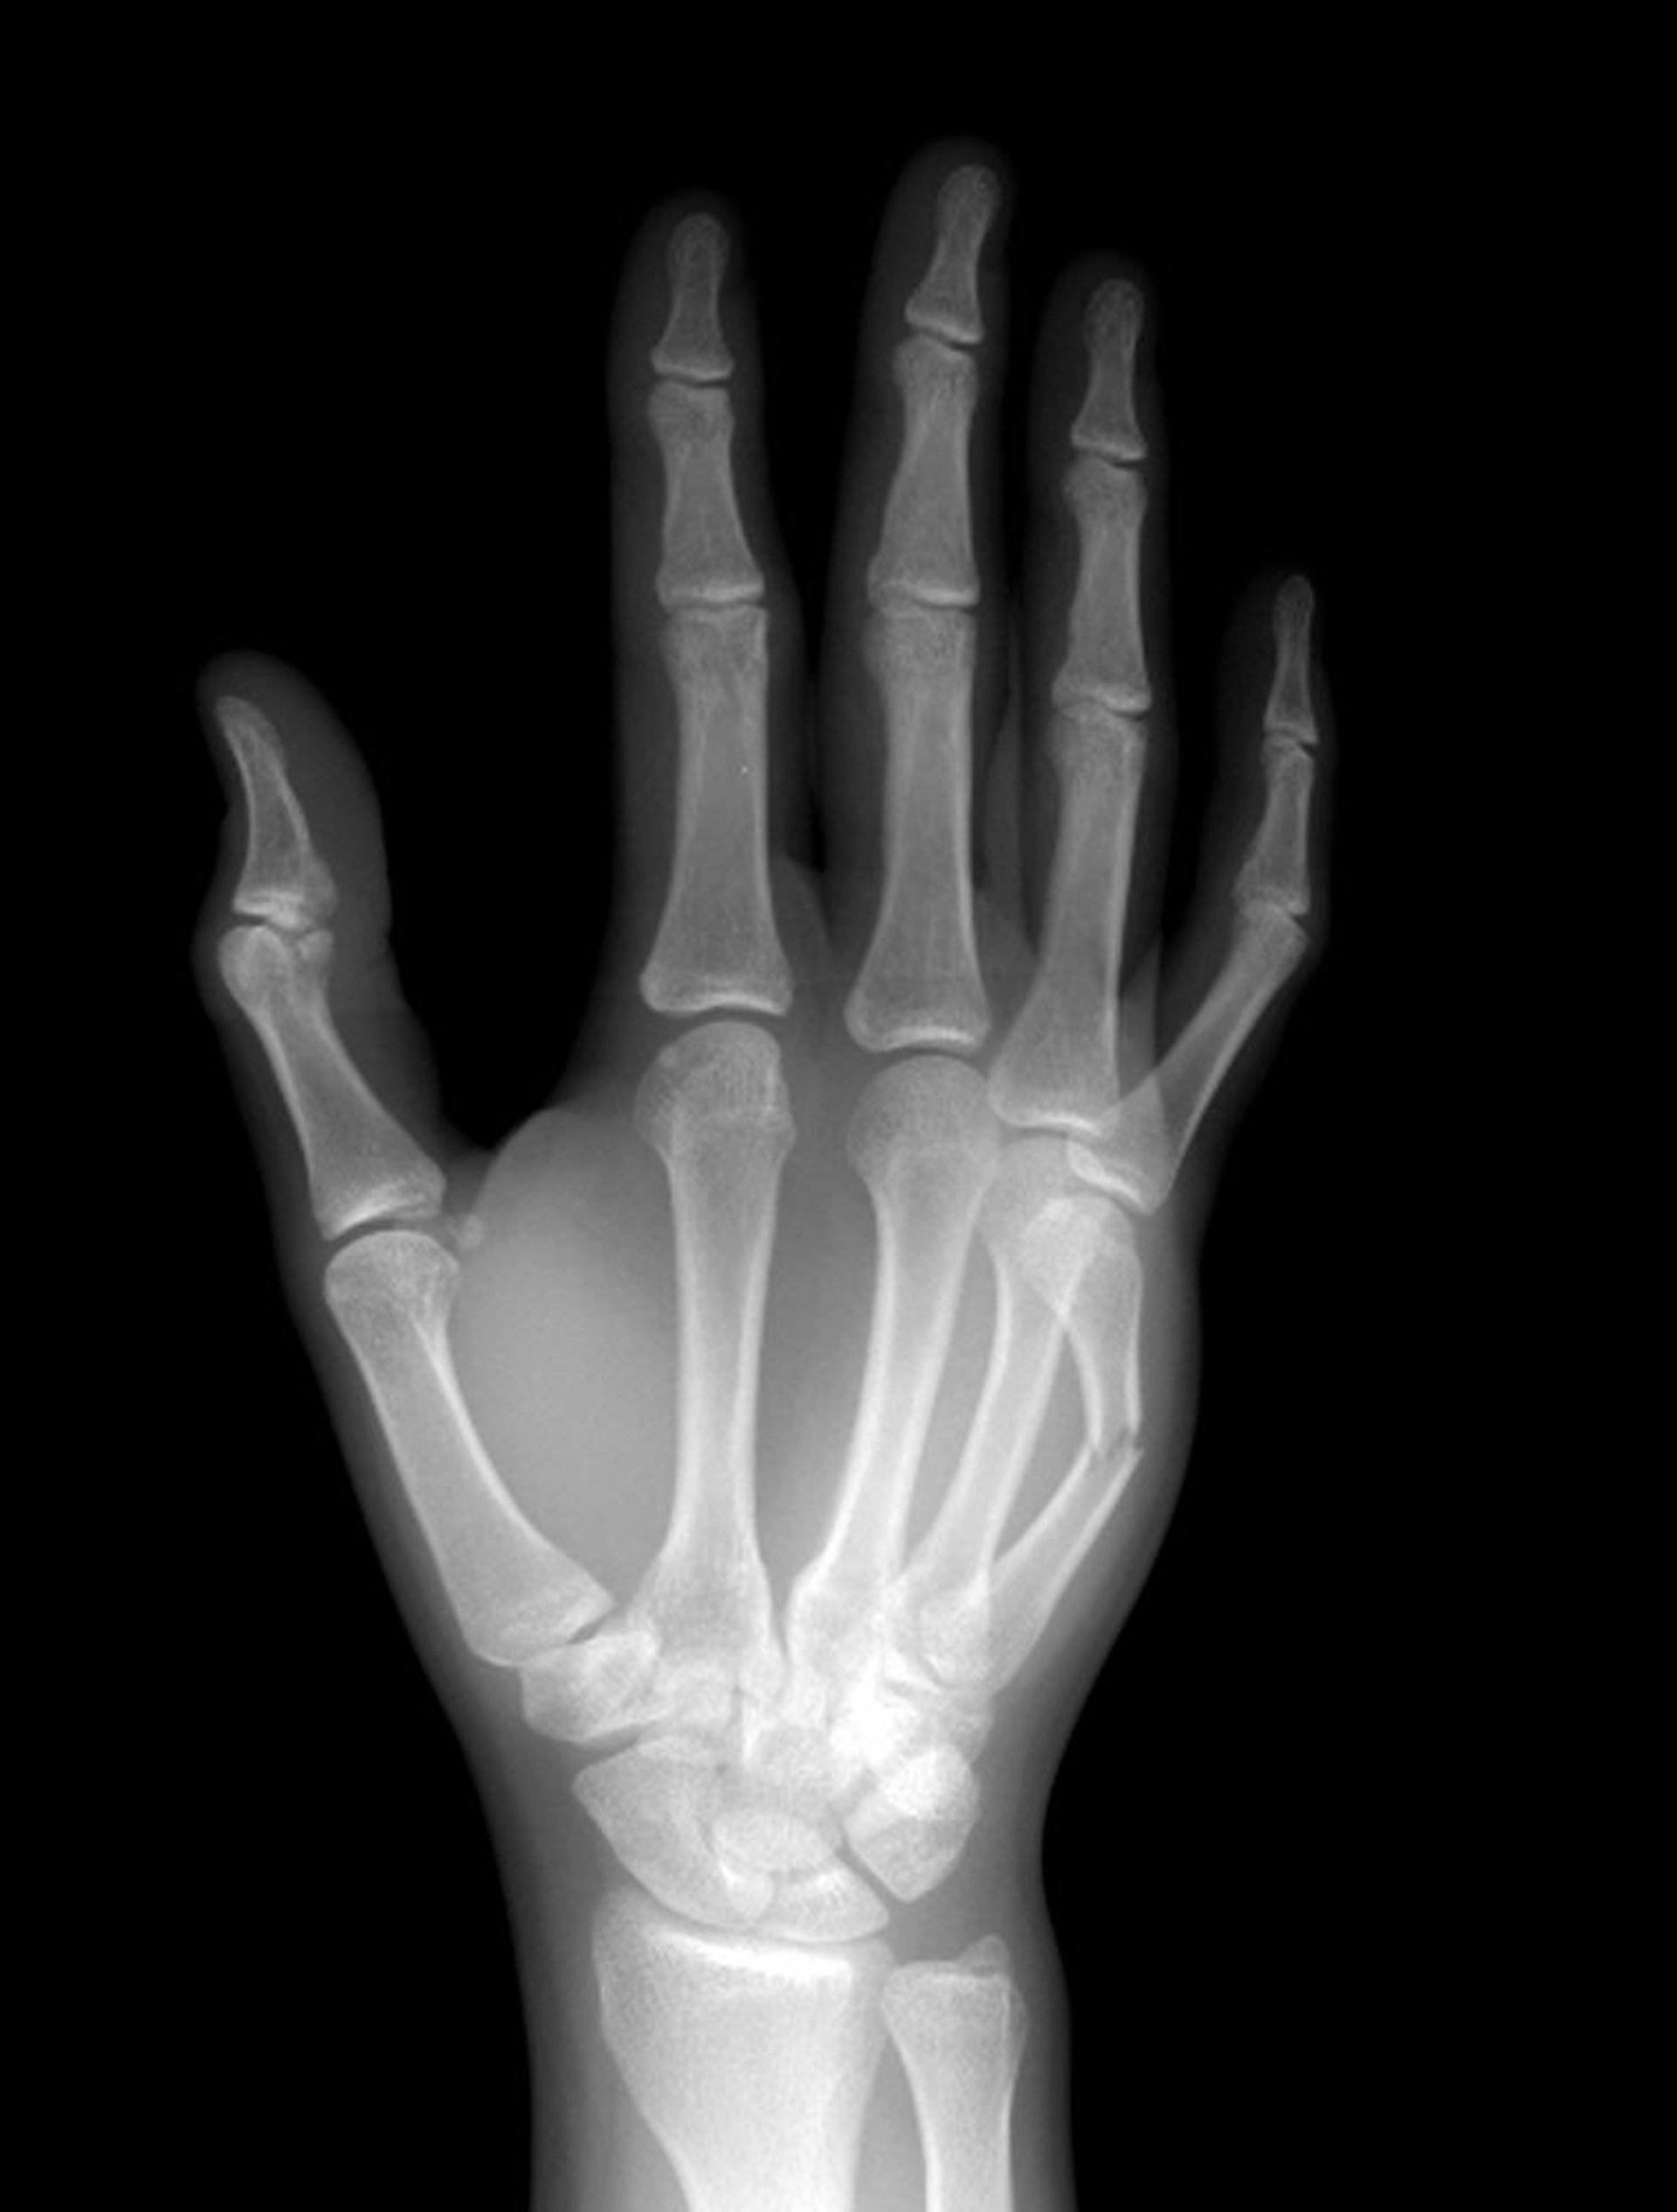

Fracturas del cuello de los metacarpianos

El cuello del quinto metacarpiano está fracturado en la mitad de la diáfisis.